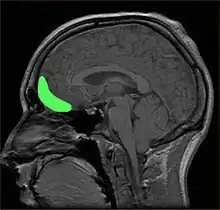

Ubicación aproximada de la COF, en una visión sagital mediante resonancia magnética de imágenes.

La corteza orbitofrontal (COF) es la región del lóbulo frontal del cerebro relacionada con el procesamiento cognitivo de la toma de decisiones. En primates no humanos, incluye las áreas corticales de asociación de Brodmann 11, 12 y 13. En los seres humanos, comprende las áreas 10, 11 y 47 de Brodmann.[1] Dado que ha sido relacionada con los mecanismos de procesamiento de la emoción y de la recompensa, algunos autores consideran que la COF forma parte del sistema límbico.

Anatómicamente, la COF se define como la parte de la corteza prefrontal que recibe proyecciones desde los núcleos mediales magnocelulares del tálamo mediodorsal.[2] Su nombre se debe a su posición, ya que se encuentra situada inmediatamente sobre las órbitas en las que se ubican los ojos. Se ha hallado una considerable variabilidad individual en la COF, tanto en primates humanos como en no humanos. En los roedores se ha encontrado un área similar.[3]